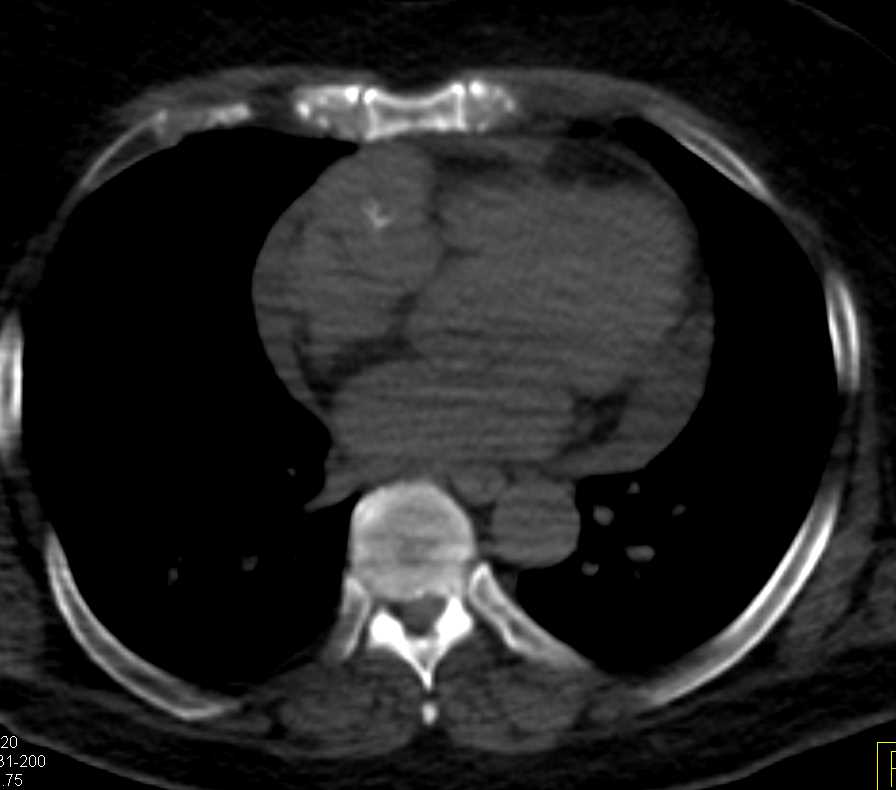

Cardiac Angiosarcoma